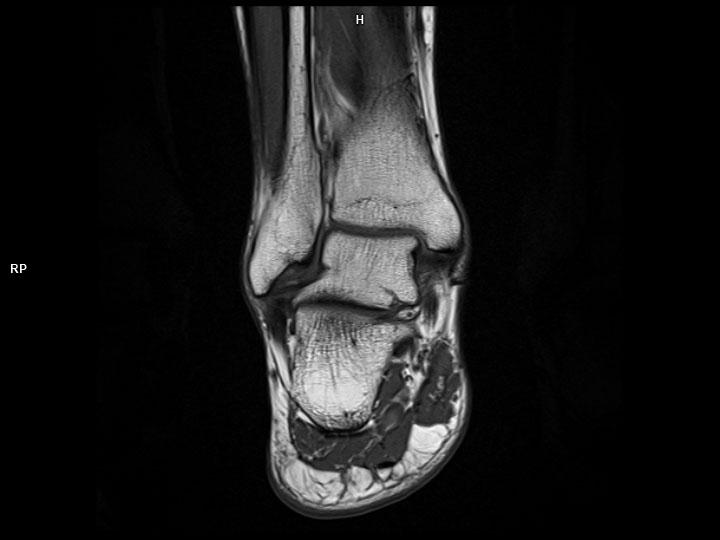

Coronal T1 TSE-MAGNETOM Lumina

Coronal T1 TSE-MAGNETOM Lumina/Coil-Foot Ankle 16/REsolution-448/Scan Time-1:46/Aceleration-p2s2